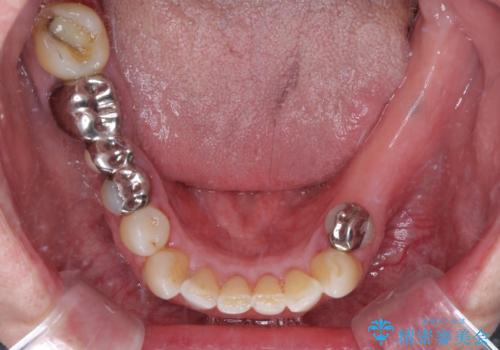

欠損の多い奥歯 インプラントによる補綴治療

治療症例の内容

- 地元ではなかなかインプラント治療を行ってくださる医院がないとのことで、転勤で東京にいる期間に治療を行いたいとのことで来院された患者様です。

上顎は左右ともに骨が少ない状態であり、特殊なドリルを用いた歯槽骨の拡大や自家骨挙上などを行いながらインプラントを埋入していくこととしました。

右下の銀歯も気になるとのことで、インプラント治療と並行してオールセラミックによるブリッジ補綴治療も行うこととしました。